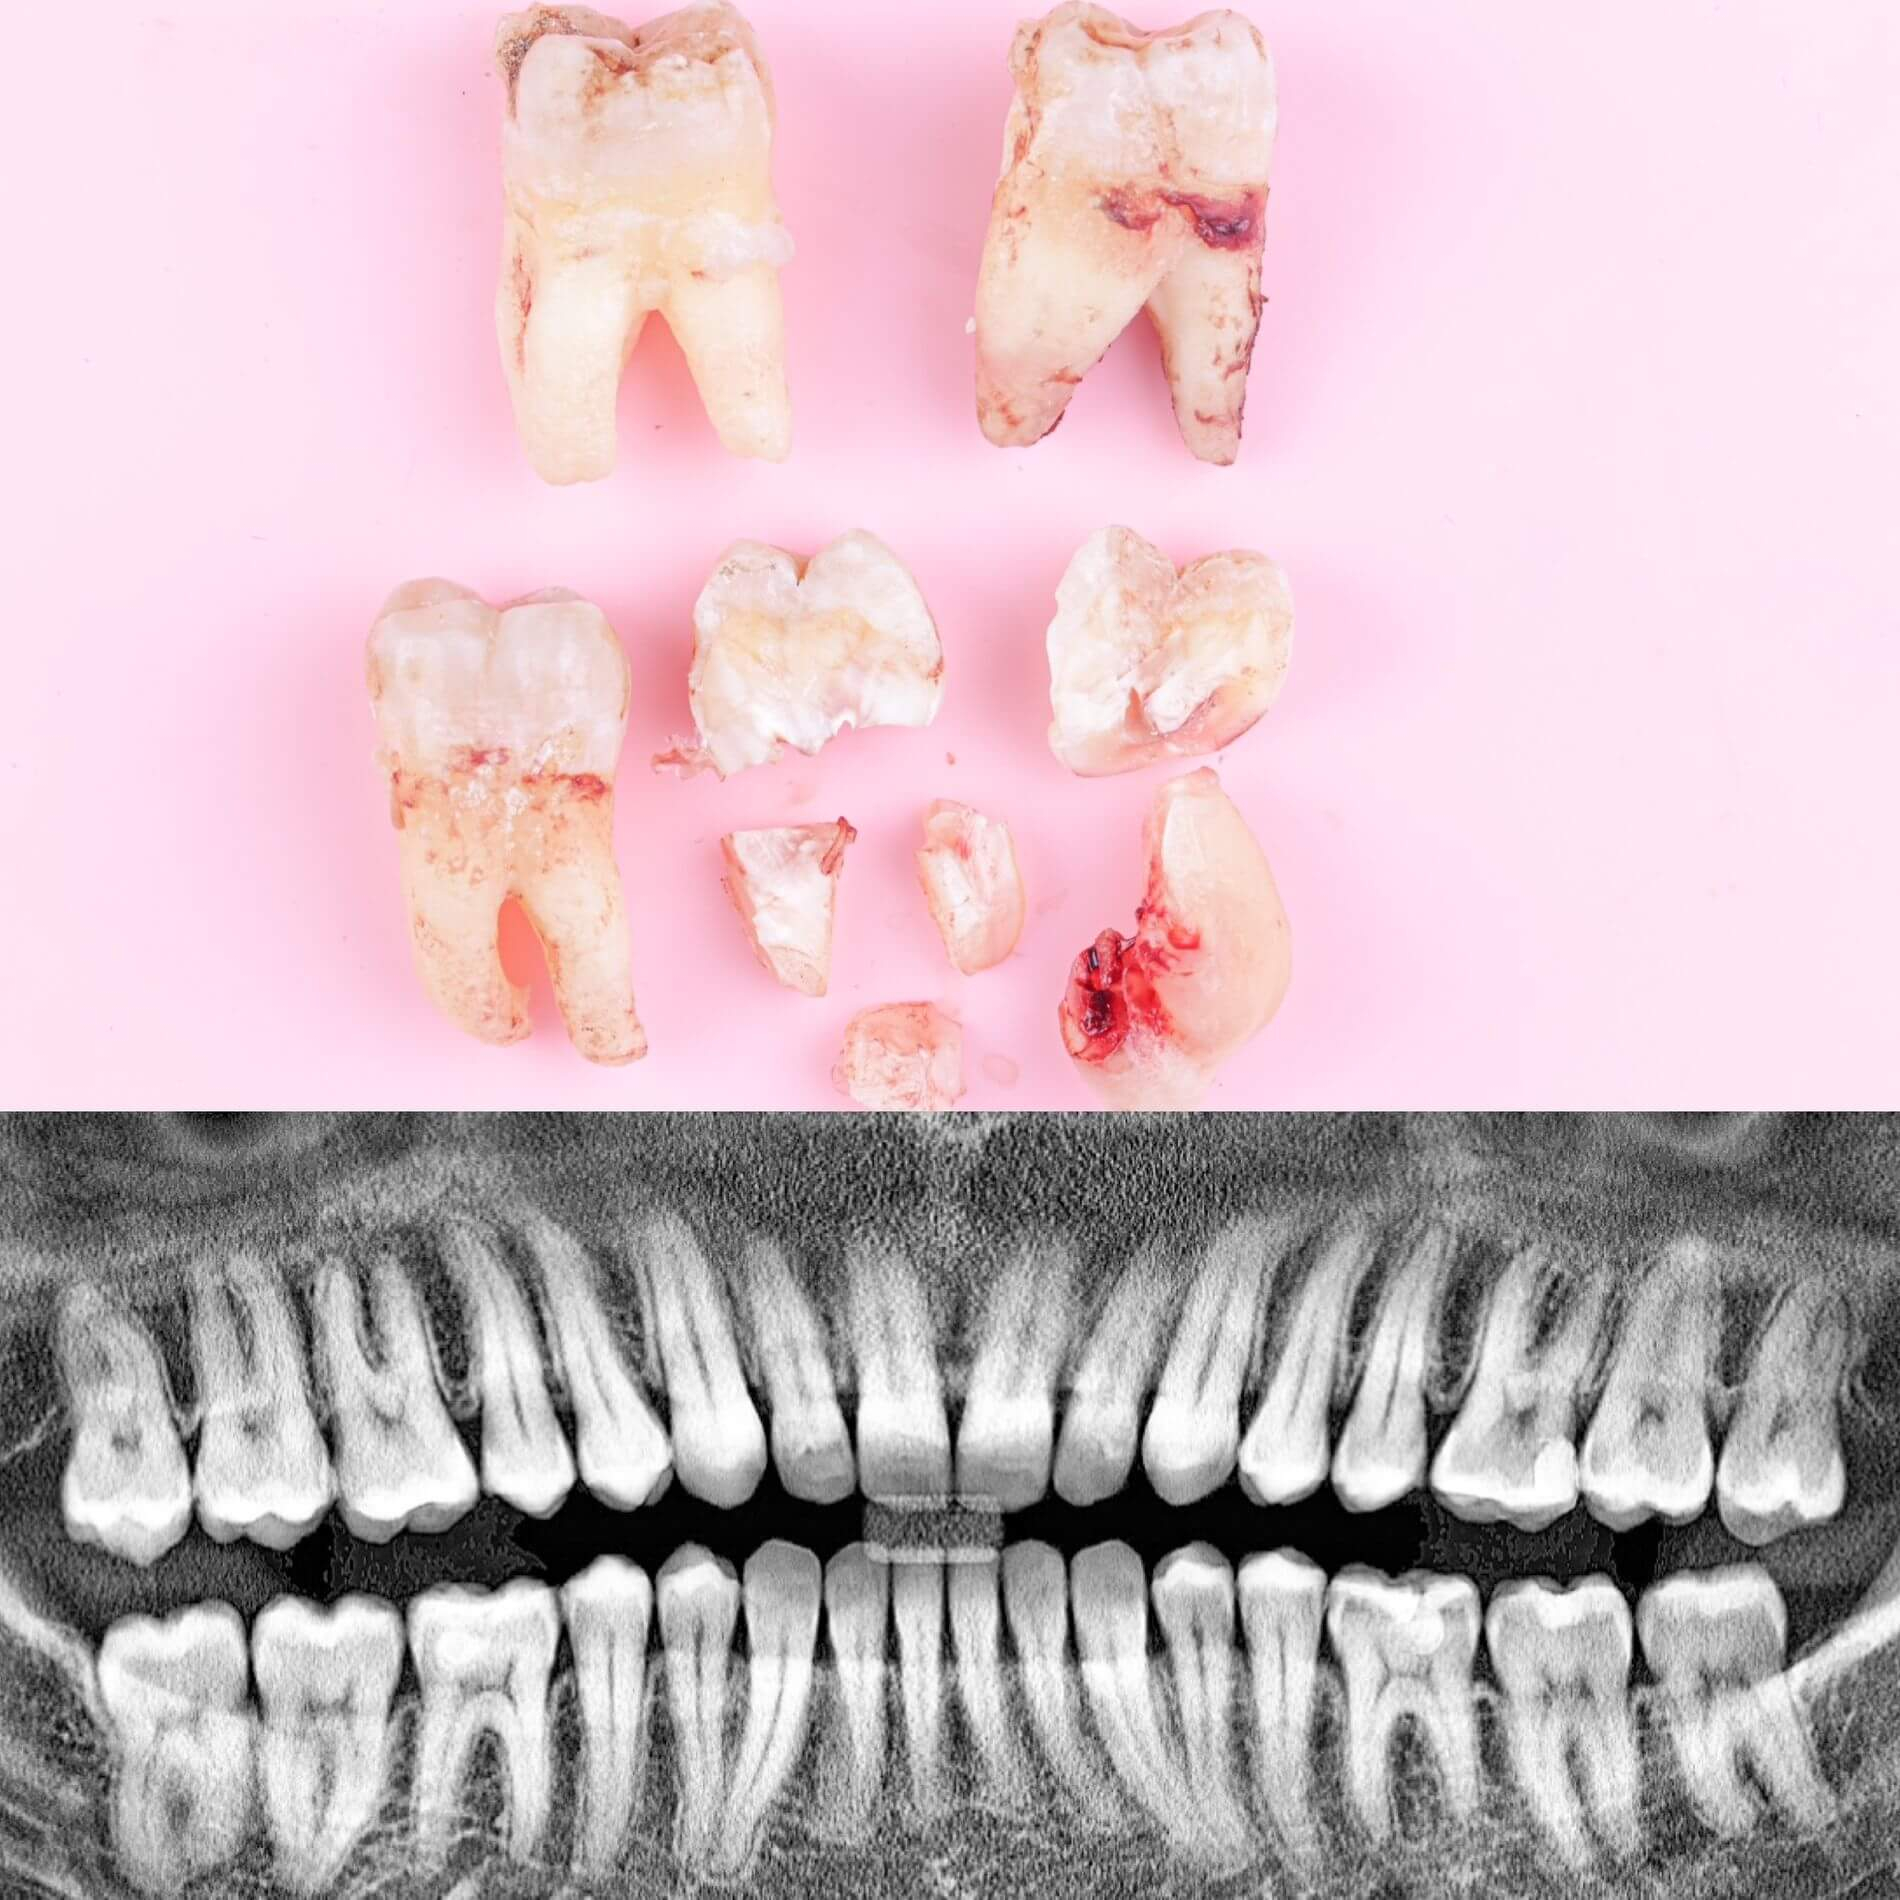

• Полное удаление зуба - если зуб полностью прорезался и имеет сросшиеся корни.

• Отдельное удаление коронки зуба и его корней - если зуб прорезан и корни растут по отдельности.

• Удаление зуба по схеме 1 или 2 с разрезом десен - если зуб прорезан частично.

• Разрез десен, освобождение зуба от близлежащей кости ультразвуком и удаление по схеме 1 или 2 - если зуб не прорезался, но беспокоит.

Удалять зуб мудрости рекомендуется тогда, когда он давит на зубной ряд и сдвигает другие зубы, причиняет боль или сам уже поврежден кариесом.

2. Развитие болезней. Зуб понемногу растет, десна образует над его верхушкой капюшон, туда забивается пища, вызывая воспаление и неприятный запах. Из-за этого также может развиться кариес.